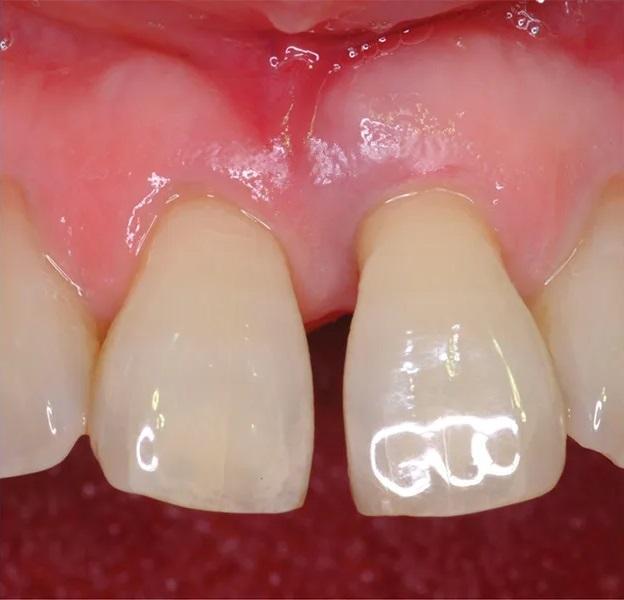

В тот же день была выполнена установка композитных виниров для маскировки диастемы по средней линии и улучшения эстетики. Заживление проходило без осложнений. Долгосрочные контрольные изображения через 5,6 лет (Фото 9) показали длительное сохранение регенерированной кости, удержание зуба и адекватный эстетический вид с практически оптимальным сосочком.